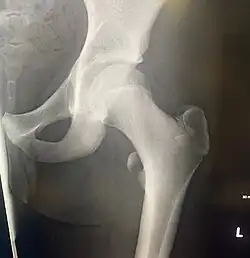

![]() Left hip-joint, opened by removing the floor of the acetabulum from within the pelvis. | |

In human anatomy, the lesser trochanter is a conical, posteromedial, bony projection from the shaft of the femur. It serves as the principal insertion site of the iliopsoas muscle.[1]

The lesser trochanter is a conical posteromedial projection of the shaft of the femur, projecting from the posteroinferior aspect of its junction with the femoral neck.[1]

The summit and anterior surface of the lesser trochanter are rough, whereas its posterior surface is smooth.[1]

The intertrochanteric crest (which demarcates the junction of the femoral shaft and neck posteriorly) extends between the lesser trochanter and the greater trochanter on the posterior surface of the femur.[1]

The lesser trochanter can be involved in an avulsion fracture.[4]